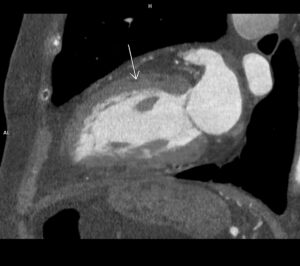

Figura 2: reconstructie oblic sagitală în planul defectului

Discuţie caz nr 90: se evidențiază o soluție de continuitate la nivelul septului interventricular în treimea medie cu diametrul de 0.2 cm ce este restricționat de trabecule ventriculare drepte și de crista supraventricularis. La acest pacient a fost descoperire întâmplătoare, indicația de efectuare a examinării cardioCT era boală coronariana cronică.

DE LUAT ACASĂ!!! Un defect de sept interventricular mic, restricționat de trabeculele VSD, este un tip de VSD în care defectul este blocat parțial sau complet de fibrele musculare și crestele din ventriculul drept, limitând fluxul de sânge prin DSV și reducând potențial severitatea shuntului. Pentru evidențierea suntului este utilă completarea cu examinare cardio-RM pentru calcularea raportului Qp : Qs prin hărți de velocitate.